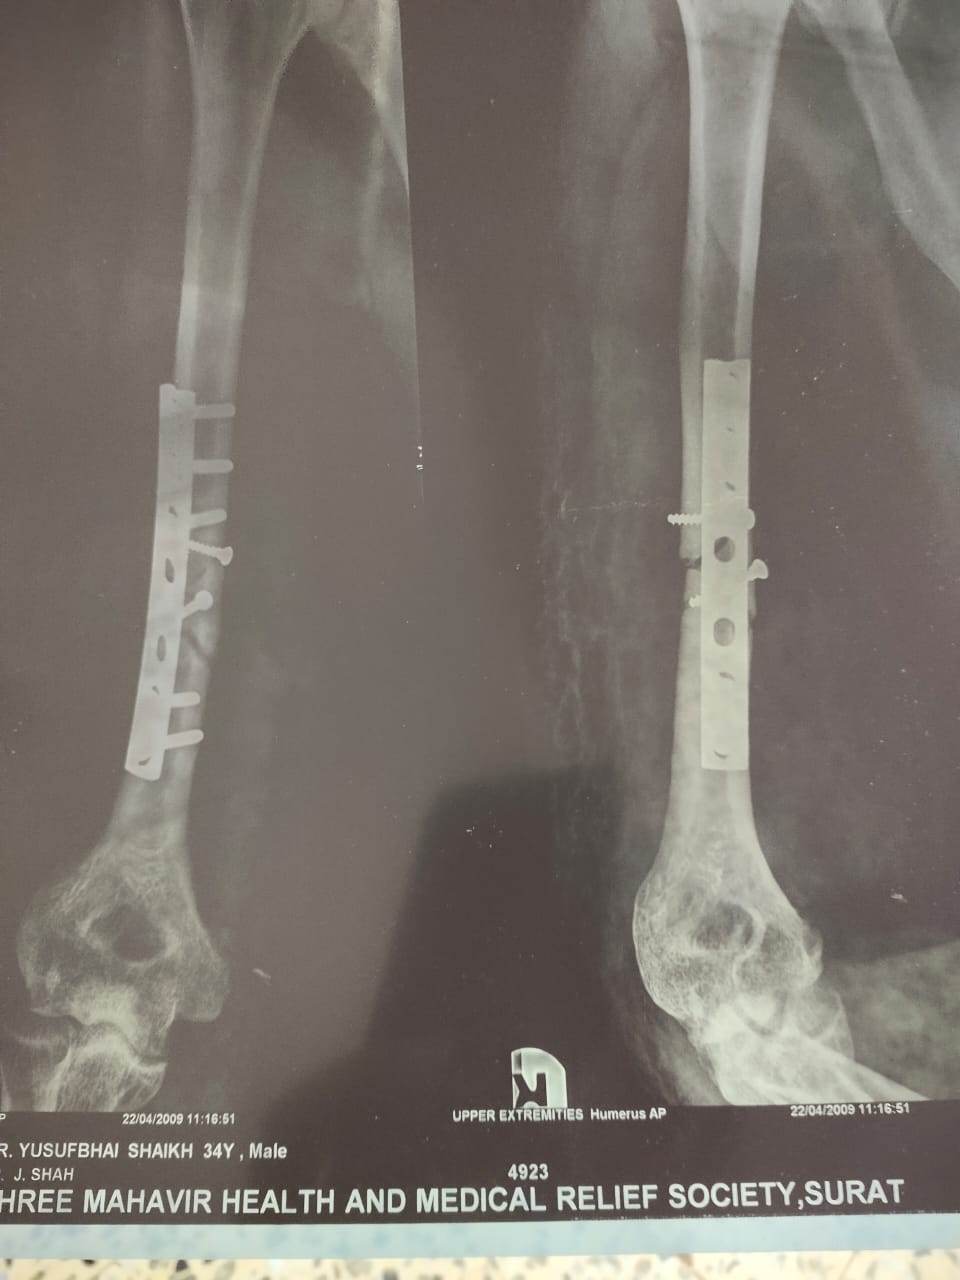

हमने इलियास से इस पूरी घटना के बारे में जानने के लिए कॉन्टैक्ट किया. उन्होंने बताया, “मैं डाभेल जाने के लिए 22 तारीख की सुबह निकला था और मैंने रास्ते में पड़ने वाले इस पेट्रोल पम्प पर पेट्रोल भरवाया. हाईवे पर गाड़ी चला रहा था तो इसी वजह से मैंने चश्मे और मास्क पहने थे. मेरा 2009 में एक एक्सीडेंट हुआ था जिसकी वजह से मैं अपने दाहिने हाथ से कुछ ठीक से पकड़ नहीं सकता हूं. मेरा ये हाथ हरकत तो करता है लेकिन उससे मैं कोई भी चीज़ पकड़ नहीं सकता. इसी वजह से मेरे दाहिने हाथ से कब नोट गिर गई मुझे पता नहीं चला. आपने अगर वीडियो देखा है तो आपको मालूम होगा कि मैंने अपने उलटे हाथ से जेब से पैसे निकाले और उन्हें दिए. इसी बीच मेरे अंगूठे में एक नोट फंस गई जिसका मुझे पता ही नहीं चला और वो नोट मेरे हाथ से गिर गई.”

इलियास से FIR के बारे में पूछने पर उन्होंने बताया, “मुझे वलसाड पुलिस स्टेशन में बुलाया गया था और पूछताछ की गई थी. तब मैंने उन्हें बताया कि मैं नवसारी नहीं गया था लेकिन हाईवे के रास्ते से मैं डाभेल ज़रूर गया था. मेरे कंधे के नीचे स्टील का रॉड डाला गया था जिसकी वजह से कभी-कभी मुझे दर्द होता रहता है और मुझे हर 2-3 महीने में डॉक्टर के पास चेक-अप करवाने के लिए जाना पड़ता है. उसके बाद वहां पर नवसारी पुलिस स्टेशन से कुछ लोग आए और मुझे नवसारी के रूरल पुलिस स्टेशन ले गए. वहां पर नवसारी के सरकारी हॉस्पिटल में ले जाकर मेरा चेक-अप करवाया गया. इसके बाद डॉक्टर ने साफ़ कर दिया कि मुझे कोई प्रॉब्लम नहीं है और कोरोना के कोई भी लक्षण नहीं हैं. मुझे तब तक इस मामले के बारे में कुछ मालूम ही नहीं था. उसके बाद मैंने अपने पैरालिसिस हो चुके हाथ के बारे में पुलिस को बताया तो उन्होंने भी माना कि मैंने जान-बूझकर नोट नहीं फेंका था. इसके बाद पेट्रोल पम्प के लोग भी वहां पर आए और उन्होंने मेरा हाथ देखा. सभी ने ये बात मान ली कि मेरे हाथ से नोट गलती से गिर गई थी. इसके बाद मुझे ज़मानत दे दी गई. मुझे डॉक्टर ने घर पर ही रहने के लिए कहा है और इसीलिए मैं अपने घर पर ही रहता हूं.” इलियास ने इस पूरी घटना के बारे में एक वीडियो रिकार्ड कर हमें भेजा है जिसमें आप उनके घायल हाथ को साफ़ देख सकते है.

इलियास के एक्सीडेंट के बाद उनके हाथों और कन्धों का एक्स-रे यहां देखा जा सकता है.